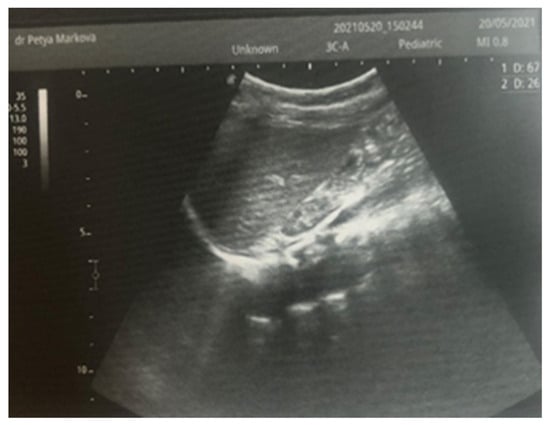

After admission to the NICU, the neonate was found febrile, with symptoms of multiple organ failure: respiratory system failure requiring treatment with Curosurf and mechanical ventilation; renal failure with symptoms of oliguria, macroscopic hematuria, and an increase in nitrogen waste products; the manifestation of neurological symptoms—muscular hypertonia and hyperreflexia, increased convulsive readiness with frequent spontaneous and provoked clonuses of the limbs. The blood tests revealed inflammatory activity—increased CRP and evidence of early nonconjugated hyperbilirubinemia. An abdominal ultrasound examination, performed 2 h after birth, found an enlarged right kidney with a longitudinal size of 6.1 cm, swollen parenchyma with a thickness of 1.8 cm, and increased echogenicity with the presence of interlobar hyperechogenic spikes—an image characteristic of the early phase of renal vein thrombosis. The left kidney—with a longitudinal size of 4.1 cm—preserved the topic, size, and echogenicity of the parenchyma, without drainage disorders, see Figure 1 and Figure 2.

Figure 1. Right kidney image taken in the 2nd hour after birth. There is an increase in size, increased echogenicity of the parenchyma, and interlobar hyperechoic spikes.